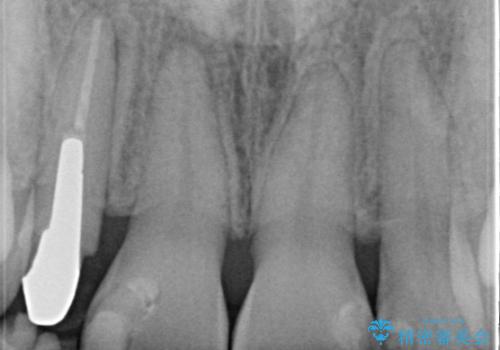

前歯が痛い。根管治療~オールセラミッククラウン

- 前歯が痛いことを主訴に来院されました。

根管治療を行った後、オールセラミッククラウン(エクセレント)にて治療を行いました。